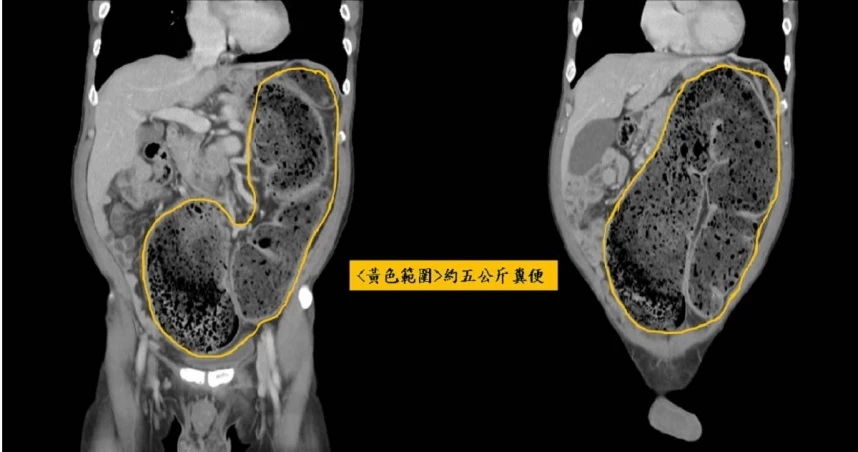

ผงะ! ชายชาวจีนไม่ขับถ่ายนาน 20 วัน อุจจาระเต็มลำไส้ลามเกือบถึงหัวใจ

ศัลยแพทย์ลำไส้ใหญ่และทวารหนัก ช่วยเหลือชายชาวจีนวัย 58 ปี หลังมีอาการท้องอืด เนื่องจากไม่ได้ขับถ่ายมานาน 20 วัน ก่อนพบมี "อุจจาระ" ตกค้างในลำไส้ และช่วงอกเกือบถึงหัวใจ น้ำหนักรวมถึง 5 กิโลฯ